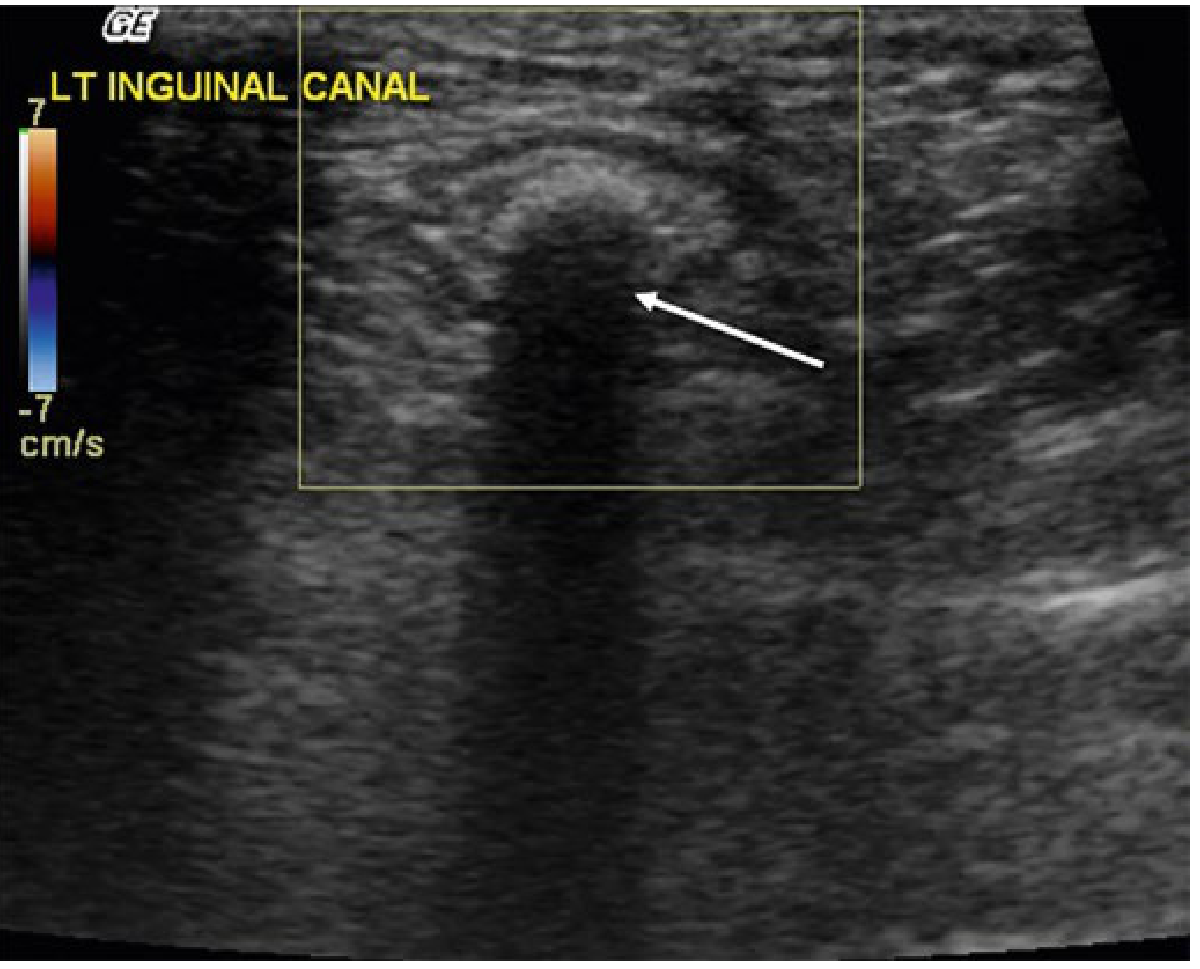

| Varicocele (in canal) | Dilated tortuous veins >3 mm, fills on Valsalva |

| Undescended testis | Oval structure in inguinal canal, smaller than normal testis |